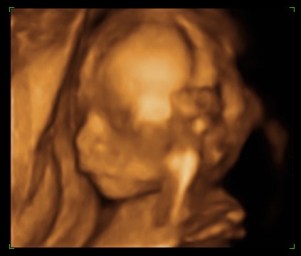

I moderni apparati consentono inoltre di arricchire la normale indagine ecografica bidimensionale con ricostruzioni tridimensionali e più recentemente anche quadridimensionali, ovvero con una modellazione solida in real-time.

L’ecografia ostetrica ha quindi un inestimabile valore diagnostico ma ha anche l’insostituibile ruolo di presentare ai futuri genitori il loro figlio, così da aumentarne la consapevolezza durante la gravidanza.